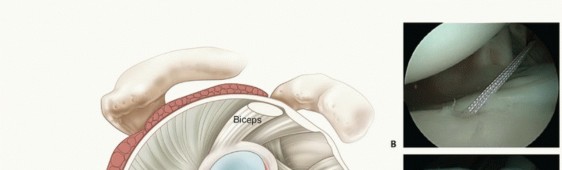

Capsular Plication (TECH FIG 2A)

A 3.0-mm Bio-SutureTak anchor loaded with no. 2 FiberWire (Arthrex, Inc., Naples, FL) is placed in the 5 o'clock position (right shoulder) for the anterior repair and 7 o'clock position for the posterior repair and the sutures brought out through the working portal (

TECH FIG 2B

).

The anchor can be placed through the cannula or percutaneously.

A soft tissue penetrator (Spectrum Suture Hook, Linvatec, Corp., Largo, FL) or crescent suture passer is passed through the labrum directly adjacent to the anchor and the inferior FiberWire on the anchor is pulled through the labrum (

TECH FIG 2C

*).

The penetrator is then used to pierce the inferior capsule in the most anterior/inferior (5 o'clock anchor) and lateral point or posterior/inferior (7 o'clock anchor) and lateral point.

Once through the capsule, a no. 1 PDS (Ethicon, Johnson & Johnson, Somerville, New Jersey) is shuttled into the joint and the penetrator is removed (

TECH FIG 2D

A suture grasper is then used to grab both the passed PDS and the labral suture and pull them out of the same portal or the working portal if two portals are used.

The PDS is then tied with a simple knot to the FiberWire, and the PDS is then used to shuttle the working suture through the inferior tuck of capsule (

TECH FIG 2E

This simple process is repeated while moving superiorly up the capsule until adequate capsular tension

was restored (

TECH FIG 2F

).23 This can be done multiple times until adequate capsular tension is achieved with each suture.

The suture is checked to ensure it will still slide, then a locking, sliding knot backed with three half-hitches is tied. The remaining suture is then cut (

TECH FIG 2G

This is begun posteriorly and inferiorly (7 o'clock anchor), working posterior with additional anchors as necessary (

TECH FIG 2H

), and then anterior and inferiorly (5 o'clock anchor) working up anterior, again using additional anchors as necessary (

TECH FIG 2I

). This would be the case if anterior instability is the most severe direction. If posterior instability is predominant, then the plication would begin anteriorly and inferiorly and then finish posteriorly.

The completed capsular plication reduces volume and improves stability (

TECH FIG 2J

TECH FIG 2 • A. Drawing depicting the single or multipleated plication. B. Placement of anchor on the rim of the glenoid. C. Passage of suture through labrum using a suture passer. D. Passage of spectrum suture passer in the capsular tissue and placement of no. 1 PDS suture. E. Passage of PDS suture into joint through capsular tissue. F. Passage of FiberWire suture through capsulolabral tissue after multipleated passage. G. Completed tied knot after first anchor and capsular plication. H. Residual labral tear remaining after first anchor placed and capsule plicated. I. Placement of second anchor as necessary for the capsulolabral repair and plication. J. Completed plication with multiple anchors.